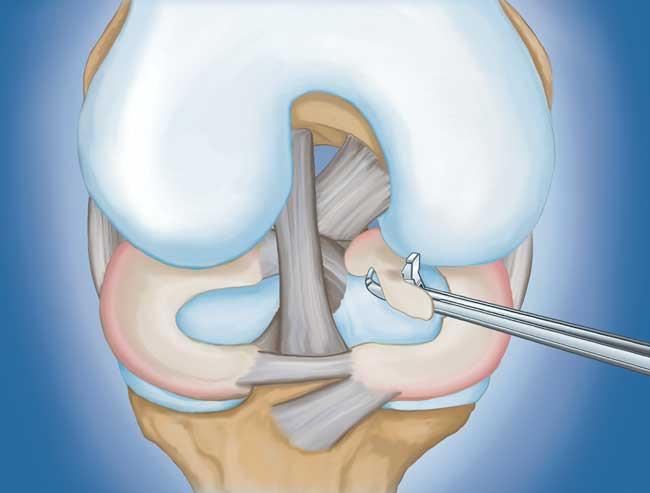

- 部分半月板切除術。 在這個過程中,受損的半月板組織被修剪掉。該程序通常允許在手術后立即負重和全方位運動。

在這段簡短的手術視頻中,半月板部分切除術期間使用電動剃須刀平滑了退行性半月板撕裂。